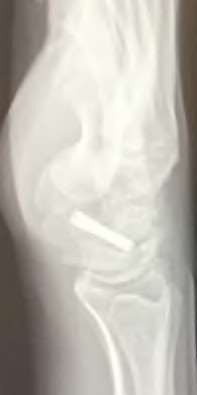

A 20-year-old park ranger trips and falls onto his right wrist with the wrist in extension and pronation. The local urgent care orders both radiographs and a CT, which you review and determine to be normal. The patient complains of ulnar-sided wrist pain. On exam, his tenderness is localized to the fovea. Ulnar deviation also causes him pain. There is no snapping sensation with wrist supination, flexion, and ulnar deviation. He otherwise has 5/5 strength to his first dorsal interosseous muscle with 4mm static two-point discrimination on the ulnar side of the 4th digit. Which of the following injuries is most likely responsible for his symptoms and exam?